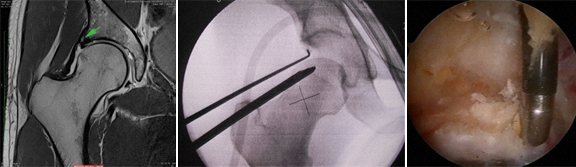

OS EXAMES MAIS ÚTEIS PARA O DIAGNÓSTICO, são:

RX: face correcta da bacia, Rx de face e perfil das ancas

TAC

RMN (com ou sem gadolineo)

ARTROSCOPIA

Por artroscopia tratam-se as lesões da cartilagem e as lesões do labro, retiram-se os corpos livres e trata-se a doença sinovial.

As lesões do labrum são frequentes e as suas causas principais são o traumatismo, o conflito femoroacetabular, a laxidez capsular e a hipermobilidade, a displasia da anca, e podem ser também de natureza degenerativa.

A lesão do labrum tem início na junção condro-labral, geralmente há preservação da inserção óssea do labrum e este tipo de rotura é mais frequente no conflito tipo CAM.

A rotura também pode ser intrasubstância do labrum e este tipo de rotura é mais frequente no conflito tipo pincer.

O labrum pode estar degenerado, pode ter rotura parcial ou completa (de toda a espessura), pode estar destacado, pode estar ossificado ou calcificado, pode ter quistos.

A rotura pode ser tipo flap com fibrilação, rotura radial, rotura longitudinal, rutura instável.